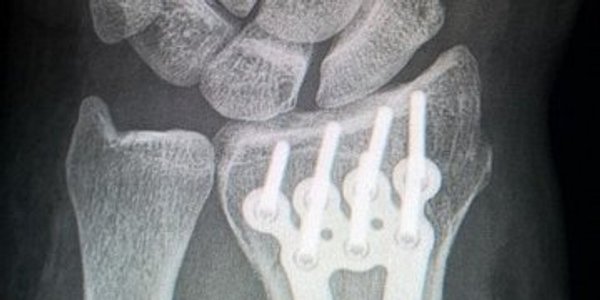

Ніяких пластин і гвинтів. Новий цинковий імплантат може зробити революцію в лікуванні складних переломів

Дослідники з університету Монаша здійснили прорив у сфері лікування переломів кісток, розробивши унікальний біорозкладний матеріал на основі цинку.